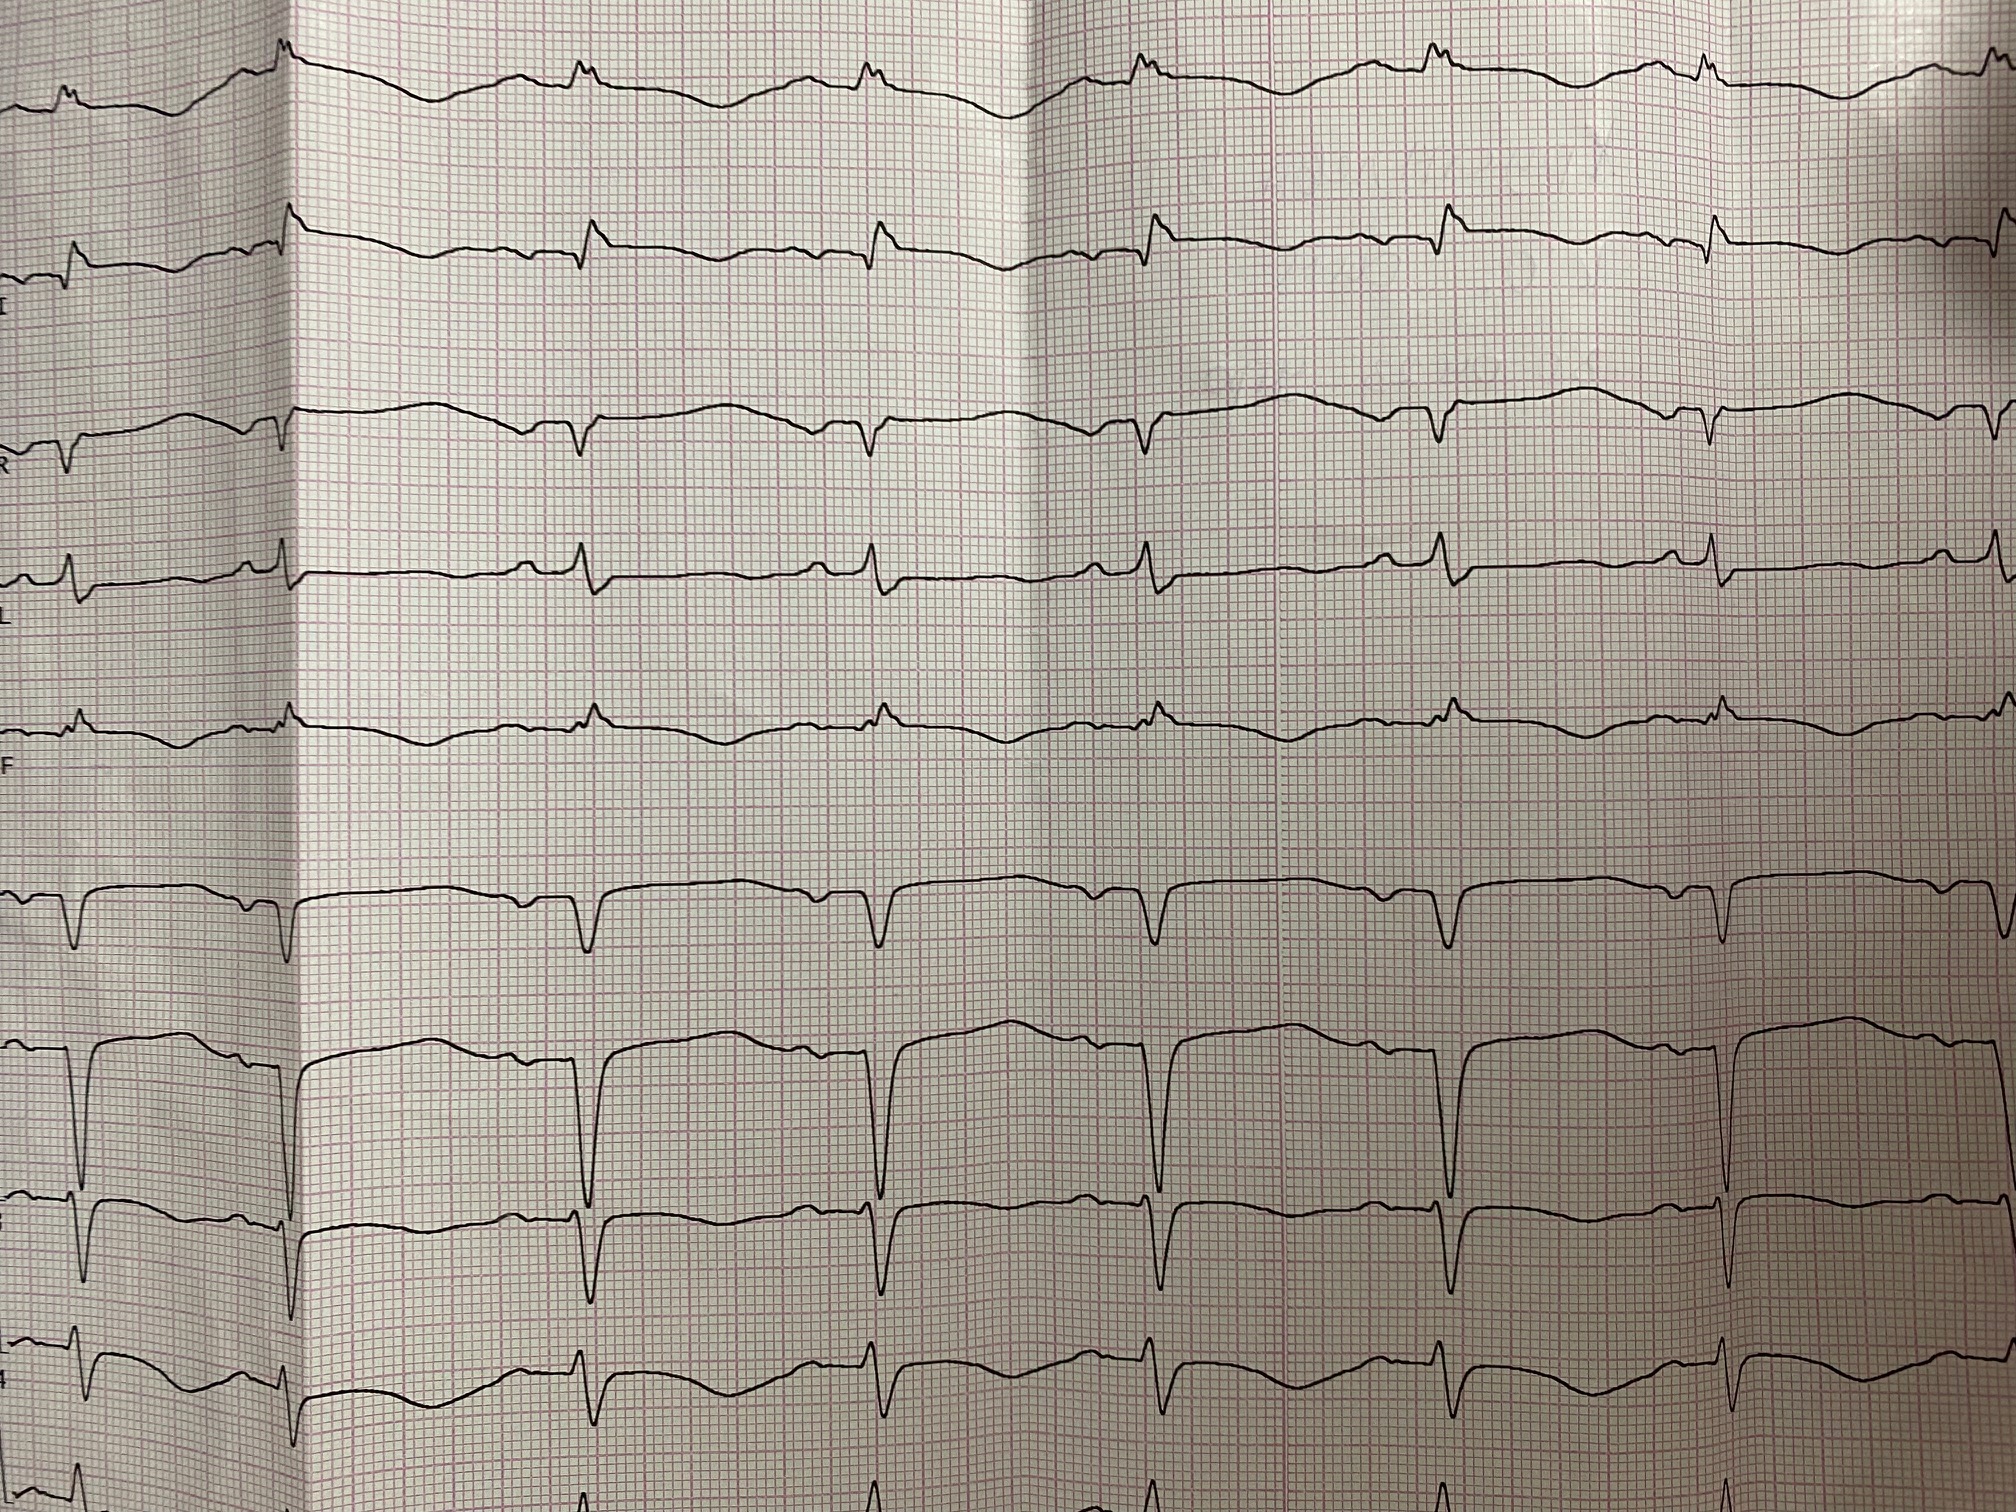

Ускоренный узловой

Обсуждалось здесь https://vk.com/club84409679?w=wall-84409679_13555%2Fall